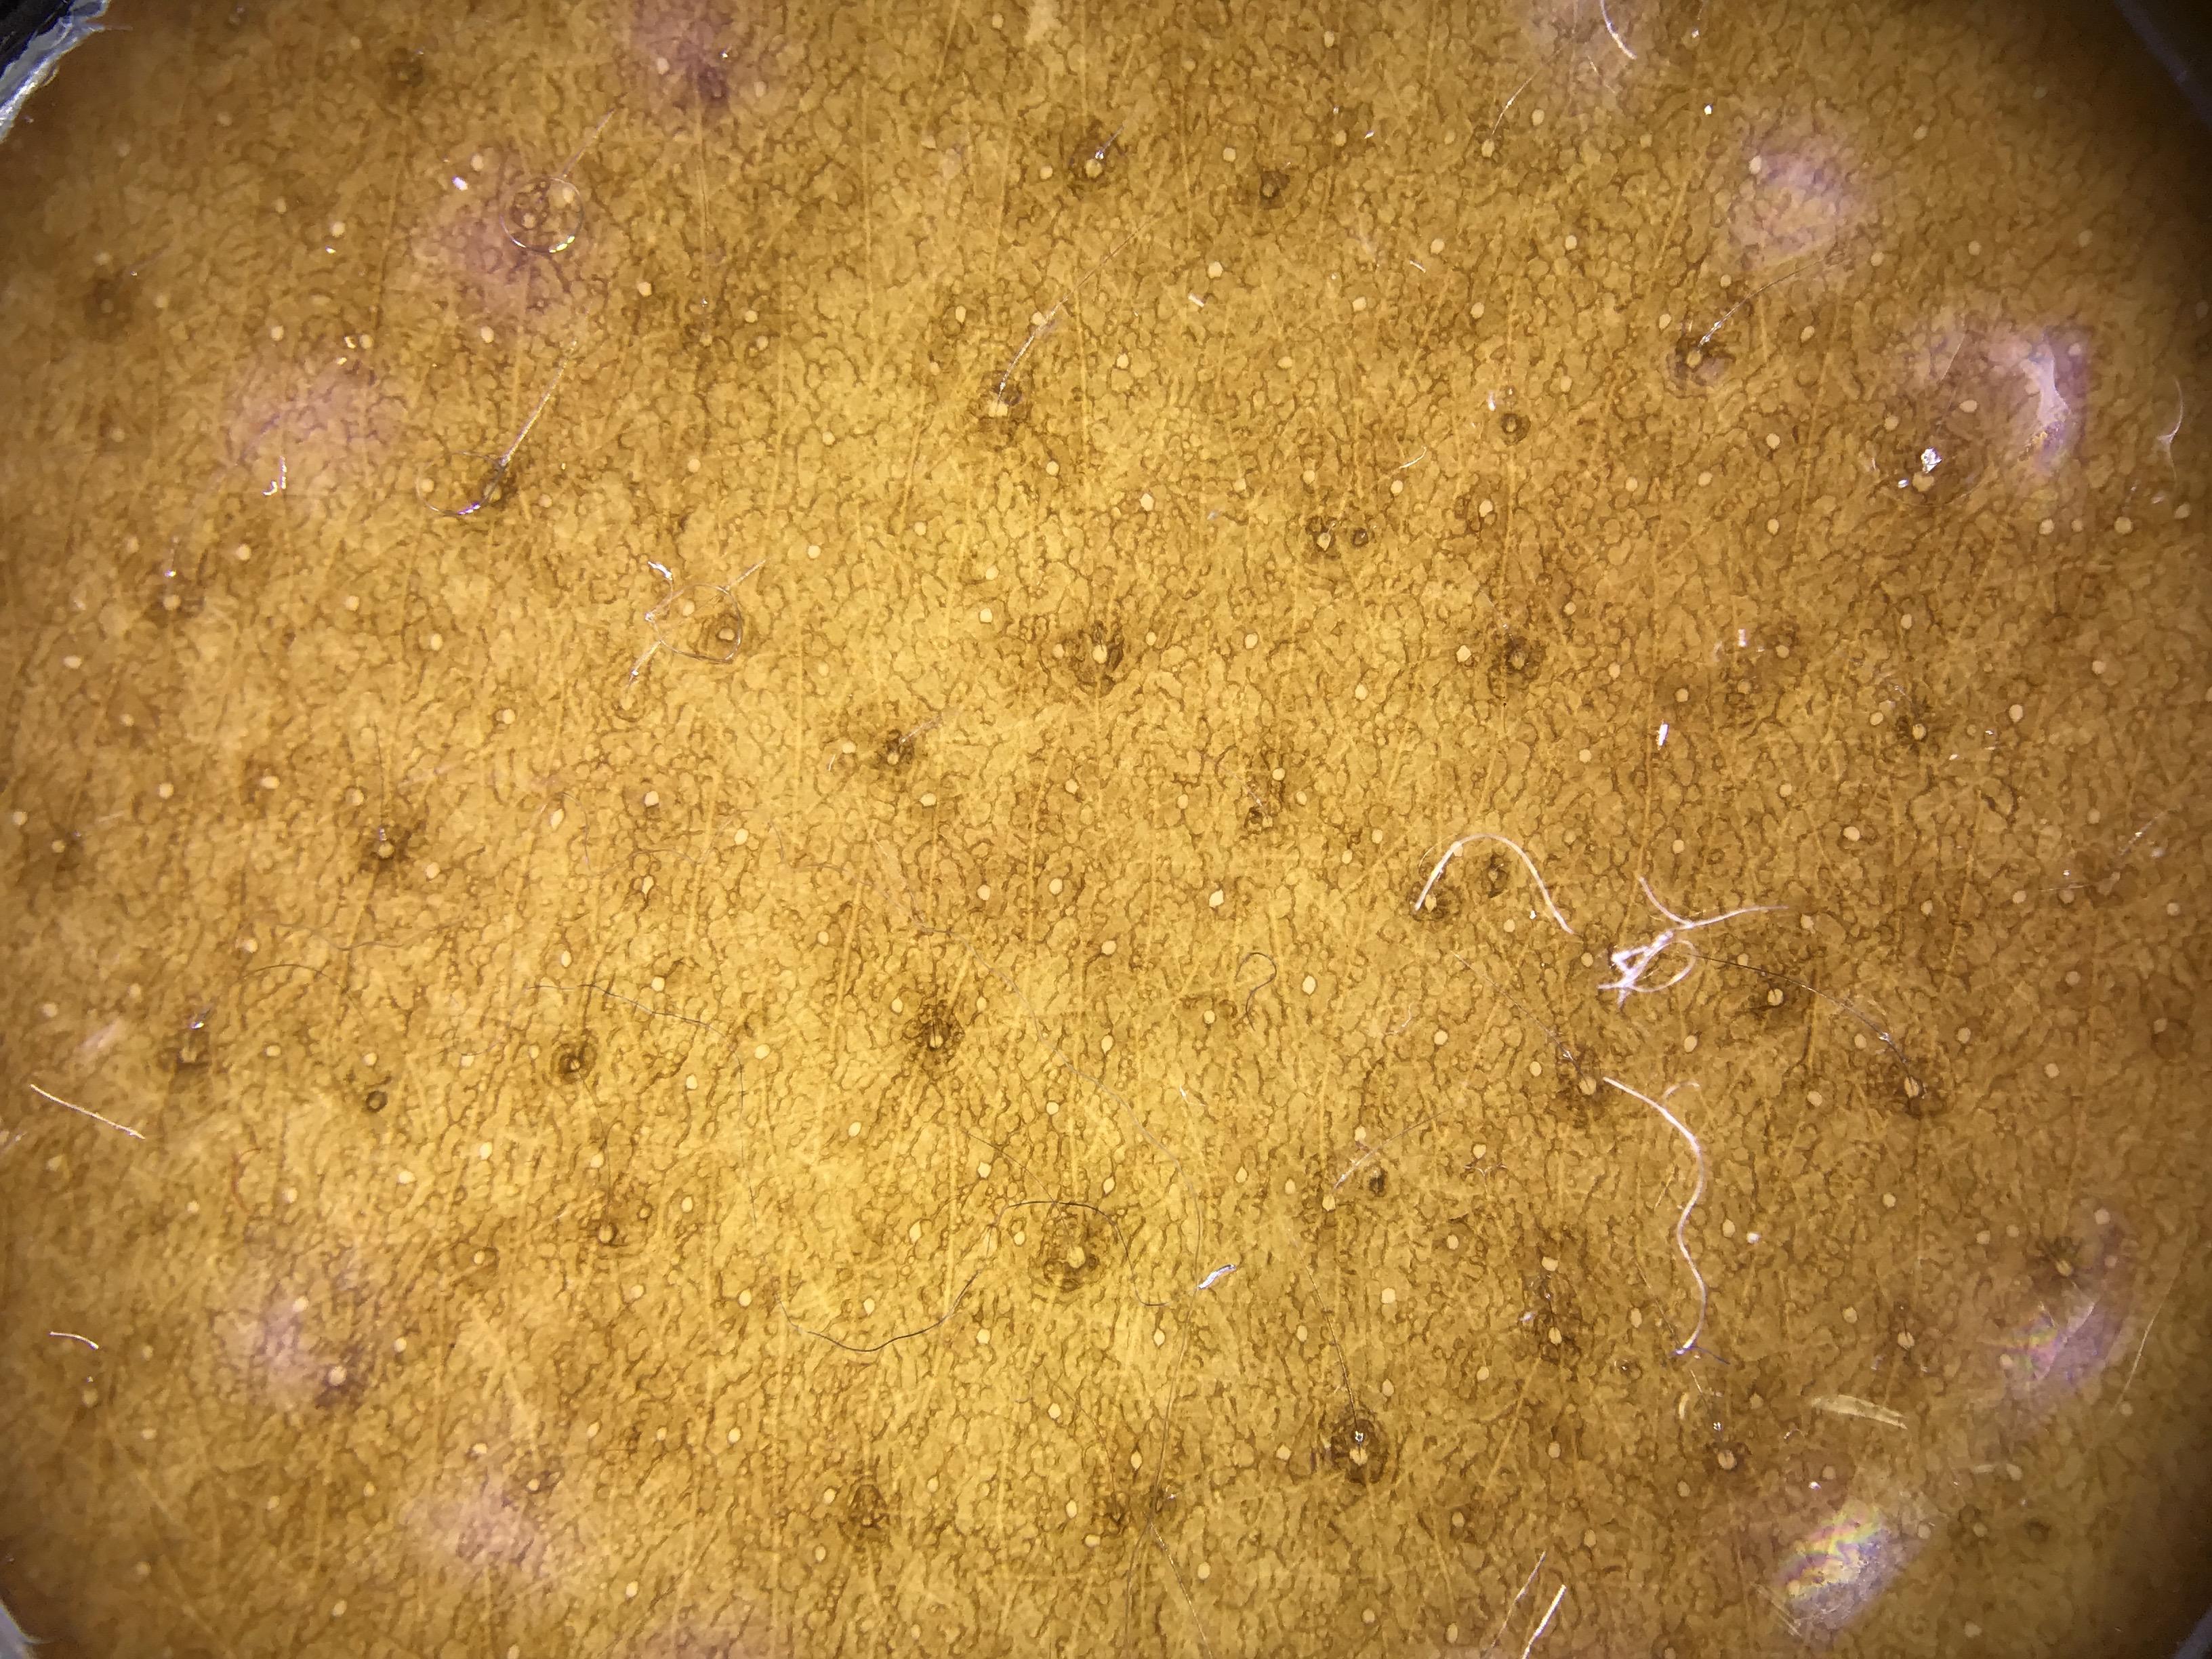

The dataset comprises both patient-level and site-level metadata for skin tone classification using the Fitzpatrick Skin Type scale, Monk Skin Tone scale, Pantone SkinTone Guide, and colorimeter readings (SkinColorCatch, Delfin Technologies). A total of 4,879 dermoscopic images are included. Skin tone assessments were collected across both lesional and non-lesional (normal skin) sites, mapped to standardized anatomic locations. All skin lesions are assumed to be benign, as they were imaged immediately following dermatologic evaluation.